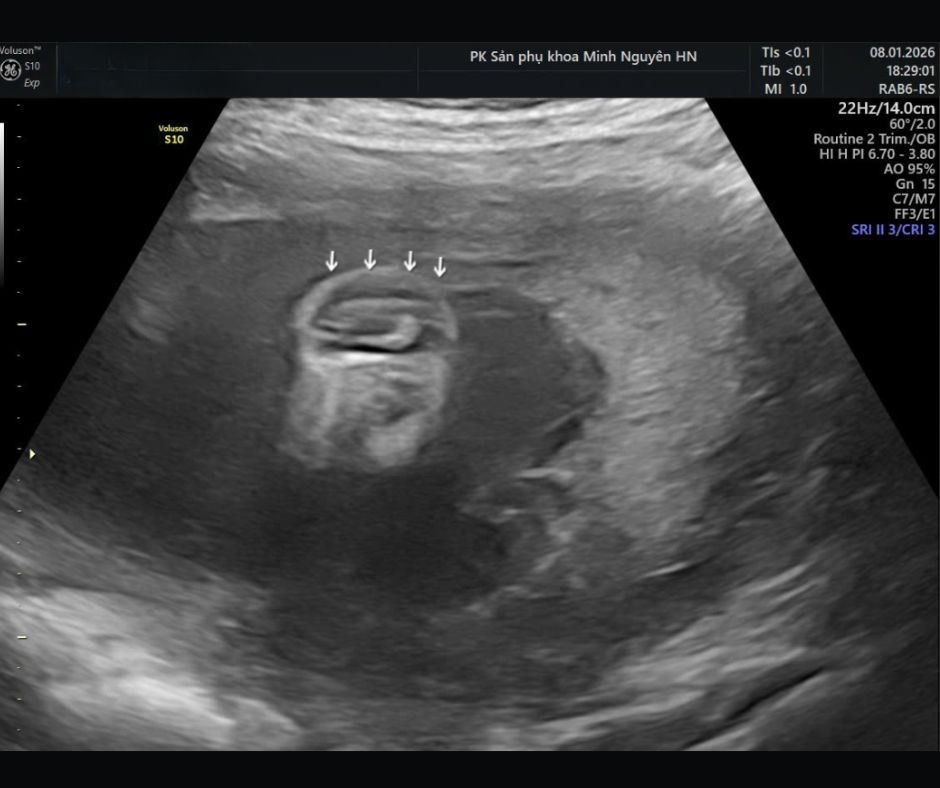

Chị H. mang thai 19 tuần, đến phòng khám Dr Tú y học bào thai với một tập hồ sơ khá dày. Trong đó có giấy siêu âm hình thái, phiếu xét nghiệm máu và usb chứa video siêu âm. Dòng kết luận khiến chị mất ngủ là nghi ngờ dị tật ống thần kinh, chẻ đôi đốt sống thể hở.

Sự thay đổi áp lực này kéo tụt phần não sau xuống thấp. Đây là cơ chế của dị dạng Chiari II. Trên siêu âm, tiểu não có thể bị ép cong và nhìn giống hình quả chuối. Đó là dấu banana sign.

Cùng lúc, xương trán hai bên có thể bị lõm vào, tạo hình giống quả chanh. Đó là lemon sign.

Ngoài ra, sự cản trở lưu thông dịch não tủy có thể gây giãn não thất. Vì vậy khi thấy dấu hiệu ở sọ não, bác sĩ sẽ rà soát cực kỳ kỹ toàn bộ cột sống để tìm vị trí tổn thương.

Nếu là chẻ đôi đốt sống thể hở, bác sĩ sẽ tập trung vào ba nhóm câu hỏi.

Tổn thương nằm ở đoạn nào của cột sống.

Có dấu hiệu kéo tụt hố sau và giãn não thất hay không.

Và dự kiến ảnh hưởng vận động, bàng quang–ruột ở mức nào.

Nếu tổn thương ở đoạn cao, nguy cơ ảnh hưởng vận động chi dưới thường lớn hơn. Nếu giãn não thất tiến triển, trẻ có thể cần đánh giá và can thiệp dẫn lưu dịch não tủy sau sinh. Nếu có bất thường kèm theo, cần mở rộng đánh giá di truyền và lập kế hoạch theo dõi sát hơn.